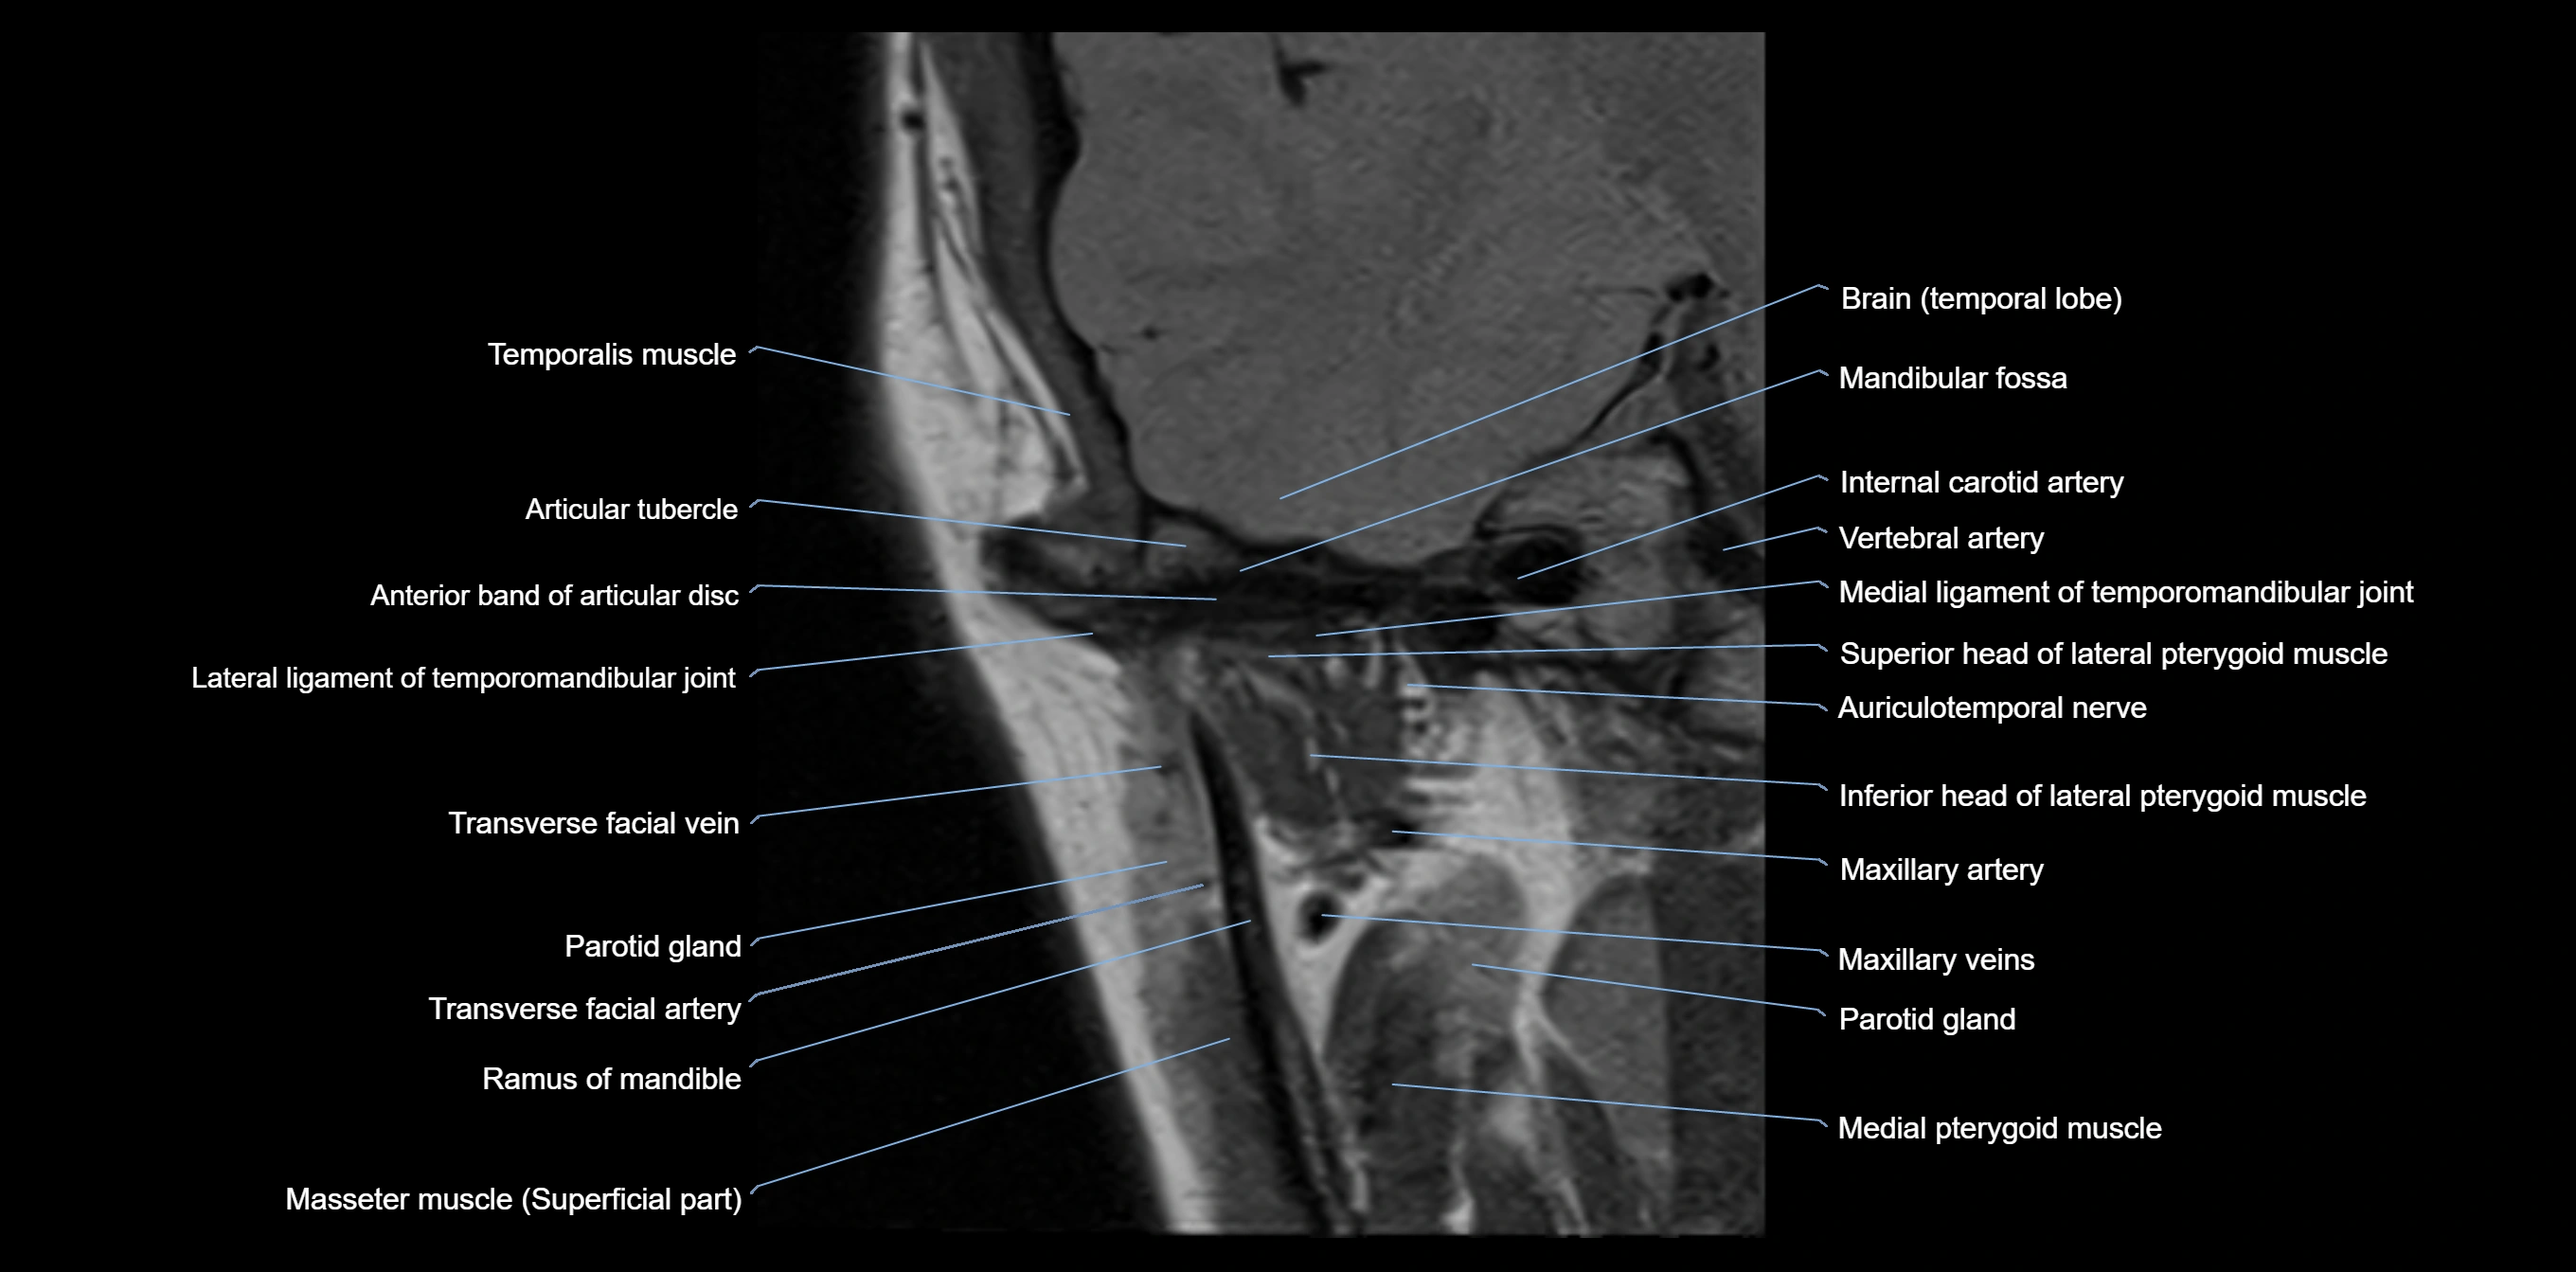

MRI appearance

T1-weighted images:

• Cortical bone: Low signal intensity

• Cancellous marrow: Intermediate to high signal depending on fatty content

• Teeth: Signal void structures

• Adjacent soft tissues: Normal gingiva and oral mucosa signal

T2-weighted images:

• Cortical bone and teeth: Low signal

• Marrow: Intermediate signal